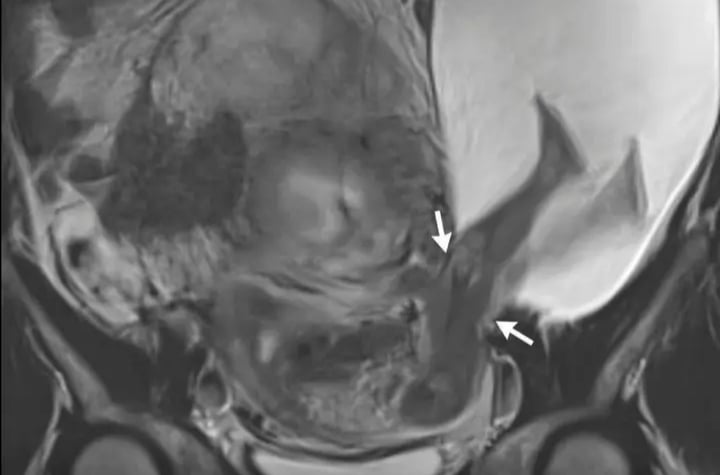

މާބަނޑުގައި އޮތް ތުއްތު ދަރިފުޅުގެ ދެފައި ފެންނަން ހުރީ ރަހިމުގެ އެތެރެއަކު ނޫނެވެ. ދެފައިވެސް ހުރީ ރަހިމުން ބޭރަށް، މަސްގަނޑު ފަޅާލާފައި ނުކުމެފައެވެ. މިއީ ހަމައެކަނި ކުއްޖާ އޮތް ގޮތް ނުބައިވުމެއް ނޫނެވެ. މިއީ ވަރަށް މަދުން ދިމާވާ، އެންމެ ނުރައްކާތެރި، ކުއްލި މެޑިކަލް އިމަޖެންސީ ހާލަތެކެވެ.

މި ހާދިސާއަކީ "ޔޫޓެރިން ރަޕްޗާ" ނުވަތަ ރަހިމު ފަޅައިގެން ދިއުމުގެ ހާދިސާއެކެވެ. ކުއްޖާ ރައްކާތެރިކަމާއެކު ބޭއްވުމަށްޓަކައިވާ ވަރުގަދަ މަސްގަނޑު ފަޅައިގެން ދިއުމުގެ ސަބަބުން، ތުއްތު ކުއްޖާ ވަނީ މައިމީހާގެ ބަނޑުގެ އެތެރޭގެ ހުސްތަނަށް ދޫވެފައެވެ. މި ހާލަތުގައި ކޮންމެ ސިކުންތަކީވެސް ތުއްތު ދަރިފުޅާއި އަދި މައިމީހާގެ ފުރާނައާ ގުޅިފައިވާ ވަރަށްވެސް ނުރައްކާތެރި ނާޒުކު ވަގުތެކެވެ.